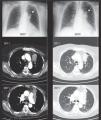

Anthracofibrosis, also known as anthracostenosis or bronchial anthracosis, is its own entity and is different from coal worker's pneumoconiosis. It is defined as a bronchial stenosis, which may vary in degree (Fig. 1) and is due to a local mucous fibrosis that also presents mucosa with anthracotic pigment1–3 (Fig. 2). Initially described by Abraham4 in 1951, it was not until 1998 that Chung5 coined the term “anthracofibrosis”. On occasions, there may be findings of distal (bronchiolar) anthracosis, but the vast majority is located at the bronchial level and is therefore described as a different entity in both its presentation as well as its causal hypotheses. This entity is more frequent in older non-smoker women from rural areas of Asia (especially the Middle East and Far East). Anthracofibrosis was not reported in Europeans until 2008 (in England), and no cases have been reported in Spain until now. It has an important relationship with pulmonary tuberculosis,6,7 an entity that is present in 30%–60%8 of the cases, which has been postulated as one of the possible causes. In other cases, anthracofibrosis is associated with the inhalation of biomass fuel smoke, especially animal manure. Radiologically, local thickening of the bronchial mucosa is usually observed, which frequently leads to stenosis, causing distal atelectasis (Fig. 1). Furthermore, it is usually accompanied by local lymphadenopathies. It commonly affects the lobar or segmental bronchi in varying numbers (more frequently between 1 and 5 segments), and does not affect the trachea or main bronchi.8

Case 3An 84-year-old woman from Madrid with no toxic habits who, during her childhood and youth (from 0 to 25 years of age) was regularly exposed to the domestic use of kerosene and coal stoves. She later worked in domestic service, with no later exposure to biomass. In 2006, she underwent studies due to triangular infiltrates in the anterior area of the left upper lobe (Fig. 1) confirmed by slow-resolution chest CT. Afterwards, 2 bronchoscopies showed edema and stenosis of the opening of the culmen segments of the left upper lobe with blackish-purple mucosa (Fig. 2), together with the growth of enterobacteriaceae and Haemophilus influenzae on respective endoscopies. The patient was treated as determined by the antibiogram, and there was a small radiological improvement; there is no later follow-up or data on the patient's evolution. The histology of the biopsies showed no evidence of malignancy, and there was no diagnostic conclusion. In 2010, the patient was again remitted for study of infiltrates in the anterior segment of the left upper lobe (Fig. 1), which did not improve after a cycle of Cefditoren. A new CT showed a heterogeneous mass/atelectasis in the anterior segment of the left upper lobe that encompassed the segmental bronchus, causing it to be obstructed, with loss of volume of the left upper lobe (Fig. 2). In addition, a 1-cm right paratracheal lymphadenopathy was observed. Given the suspicion for neoplasm, another bronchoscopy was performed (Fig. 2), which showed a black vegetative mass that stenosed the anterior and apical-posterior opening of the left upper lobe. Upon biopsy, the tissue showed mucosa with fibrous chorion and abundant anthracosis with no data for malignancy. The cultures were negative. Tuberculosis bacilli were not isolated, and therefore specific treatment was not started.

DiscussionAnthracofibrosis is an entity that has not been reported in our setting. It is characterized by black pigmentation of the bronchial mucosa due to anthracotic deposits9 together with local inflammation and finally fibrosis that distort and stenose said bronchus (Fig. 2) with potential atelectasis of the tributary parenchyma (Fig. 1). The cause of said entity has not been completely clarified, although various hypotheses have been postulated. First is the tuberculosis hypothesis,6,7 explained by the tuberculous reactivation of lymphadenopathies adjacent to the bronchus that infiltrate and continuously fistulize the wall of the bronchus with caseous granulomatous inflammation and later local fibrosis.4 Anthracotic pigmentation is supposedly due to the fact that the lymph nodes of people exposed to smoke or coal have anthracite particles responsible for the coloration as they are in contact with the bronchial wall. This hypothesis would explain the highly frequent (30%–60%)8 association of anthracofibrosis and tuberculosis, as in the first case described. Different publications are also in favor of this hypothesis, reporting partial radiological improvement after tuberculostatic treatment,5,7 although there is no evidence of resolution with said treatment.